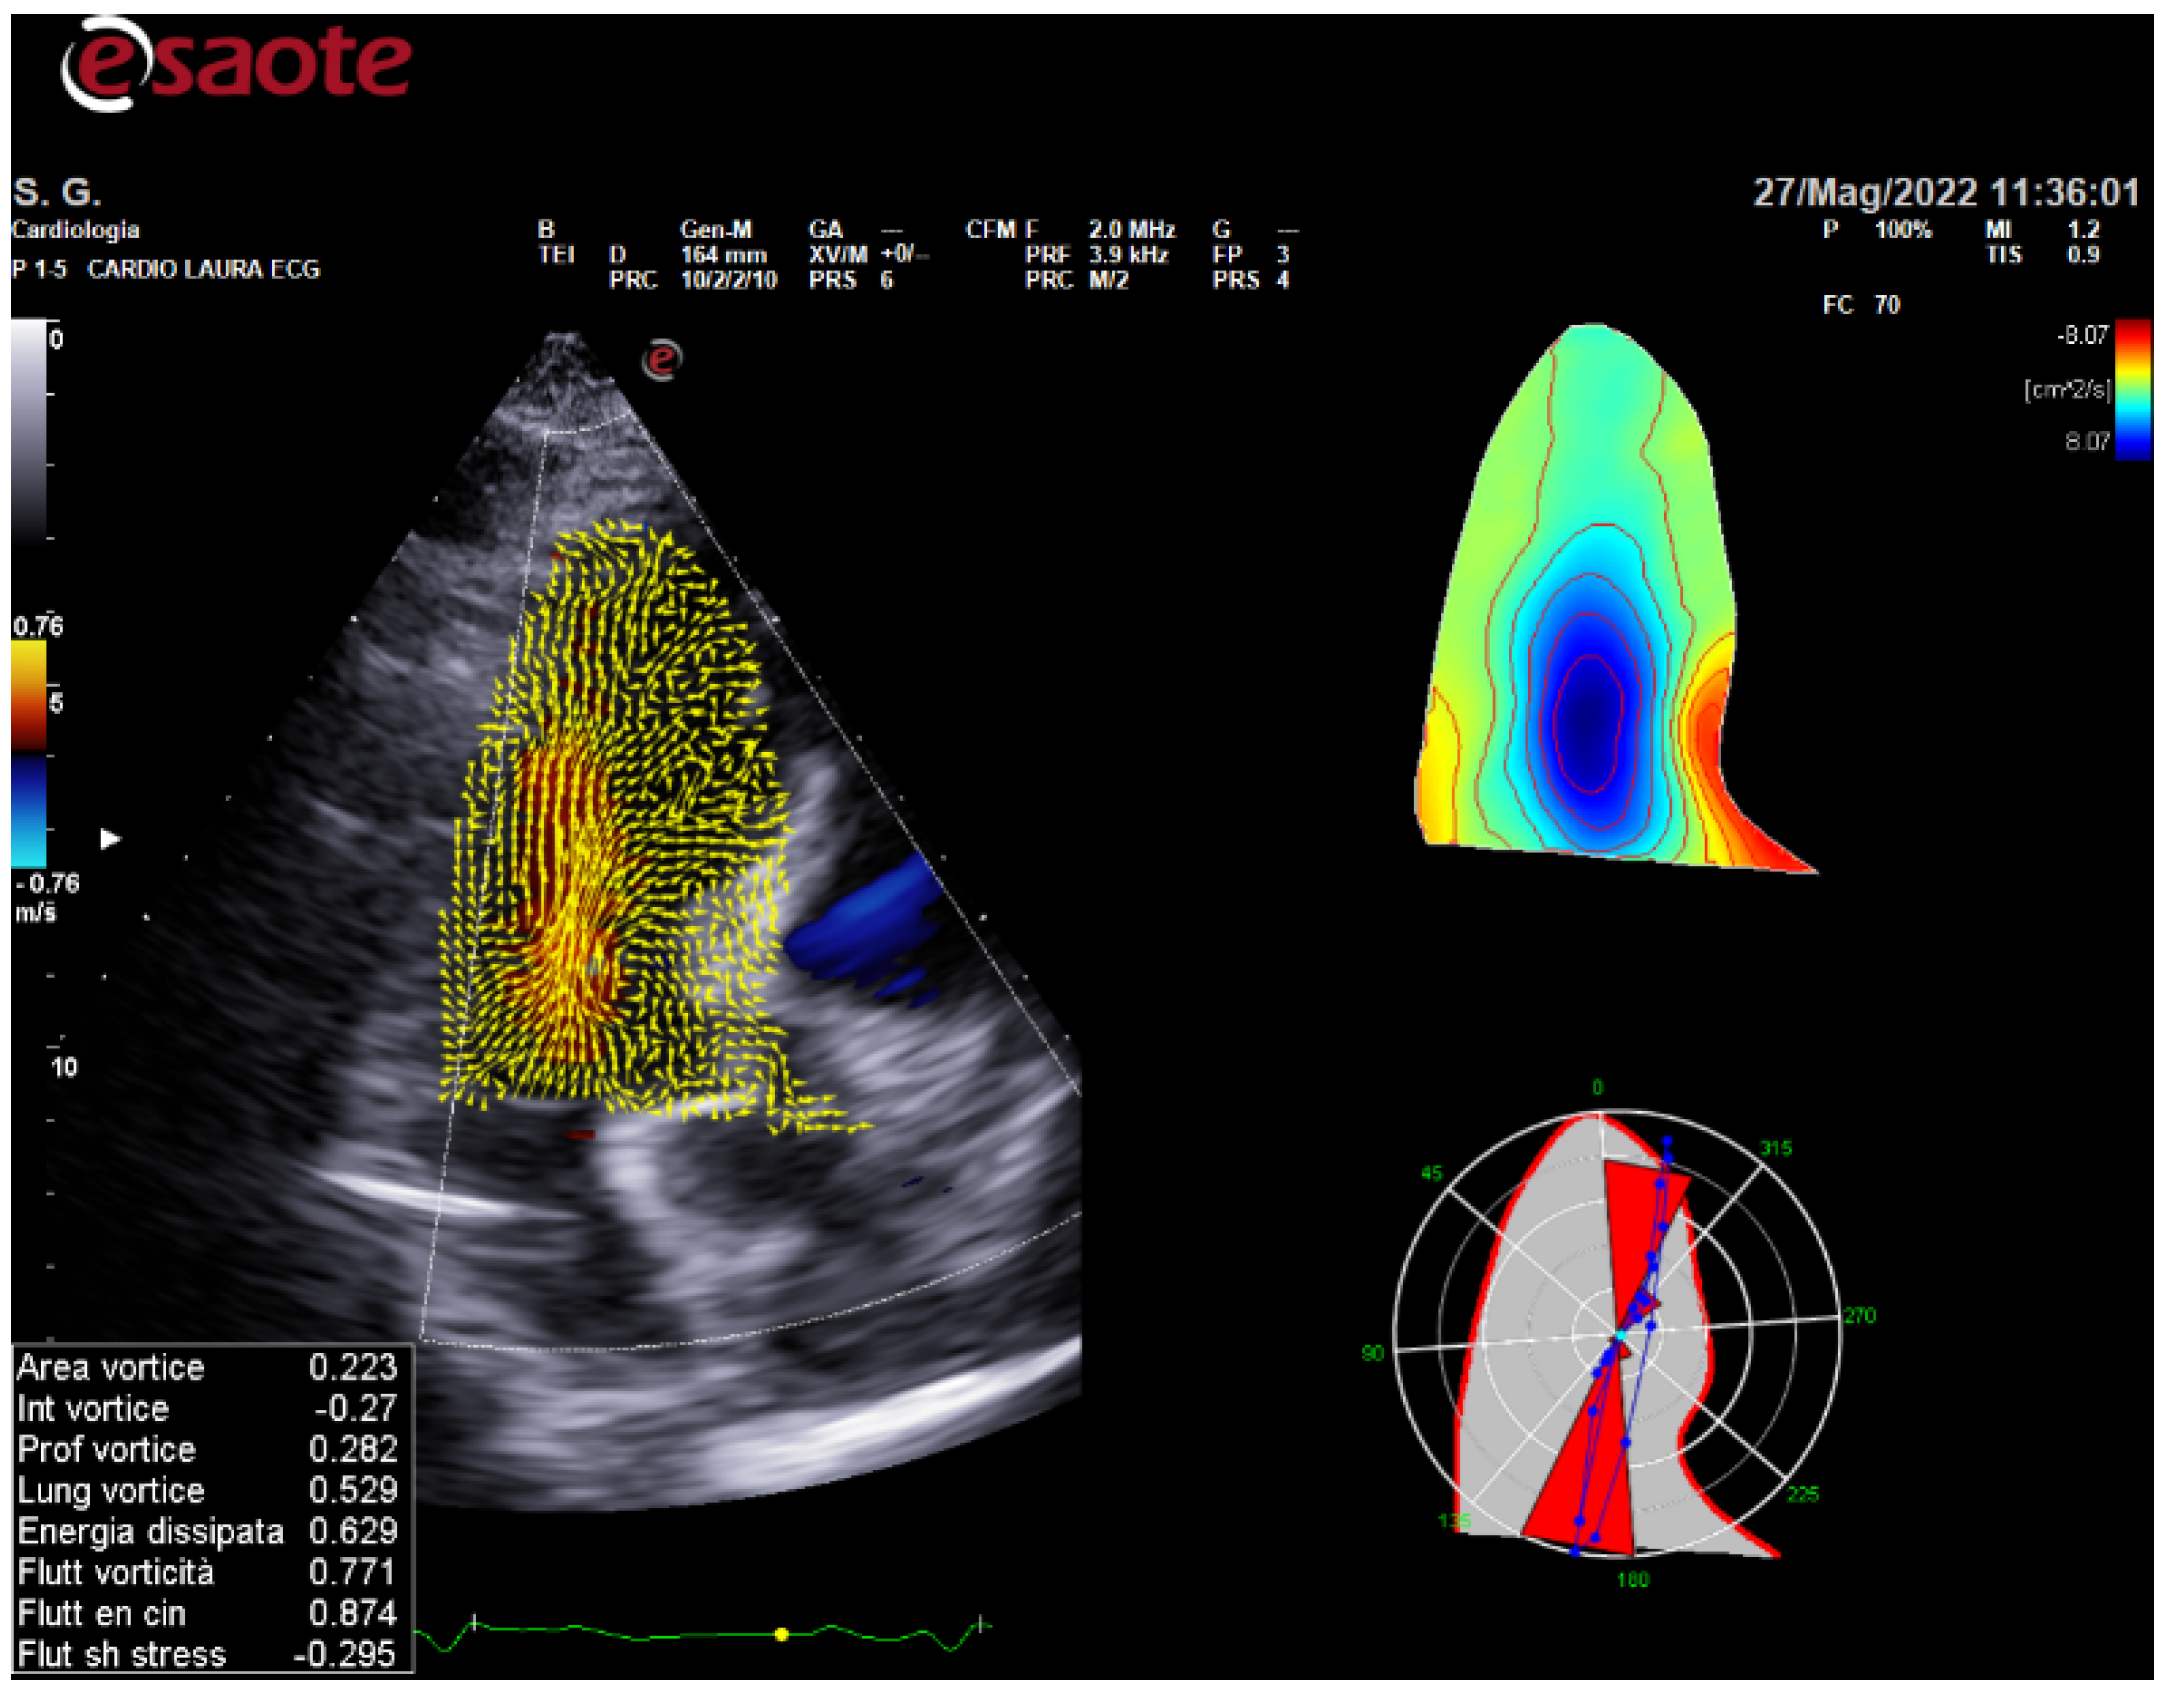

- Fiorencis, A.; Pepe, M.; Smarrazzo, V.; Martini, M.; Severino, S.; Pergola, V.; Evangelista, M.; Incarnato, P.; Previtero, M.; Maglione, M.; et al. Non-invasive Evaluation of Intraventricular Flow Dynamics by the HyperDoppler Technique: First Application to Normal Subjects, Athletes, and Patients with Heart Failure. J. Clin. Med. 2022, 11, 2216. [Google Scholar] [CrossRef]